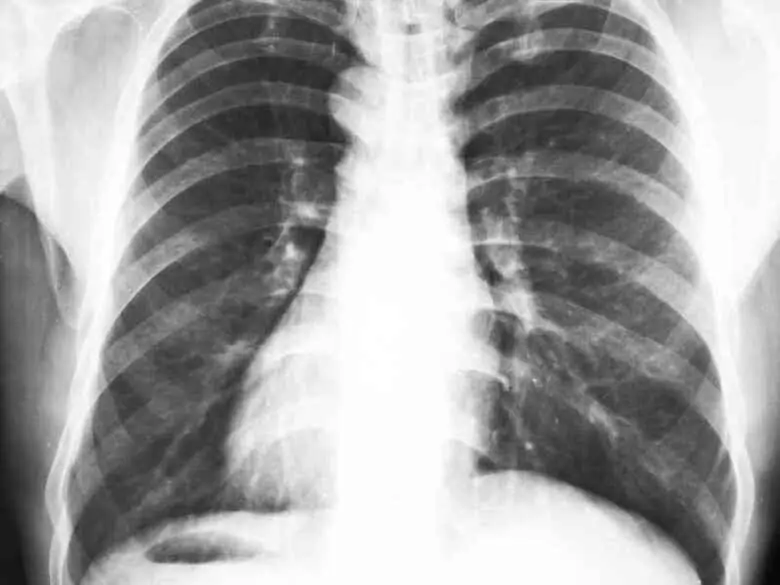

Röntgenaufnahme der Brust in der Kardiologie

Röntgenaufnahme des Brustkorbs

Chest Röntgen image in cardiology - Symptomen und ablauf